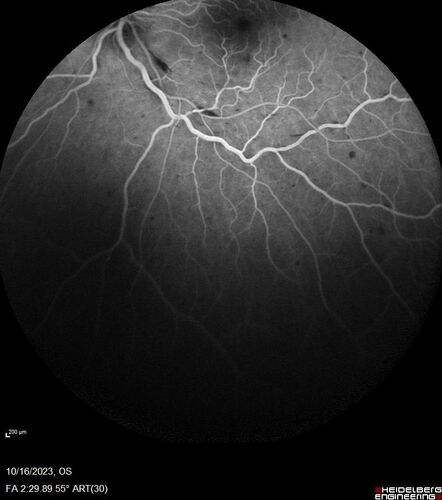

Central Retinal Vein Occlusion with cilioretinal artery occlusion

63 year old female who lost vision in the left eye 2 days ago. She was in the emergency room and had a lot of tests done which were all reportedly normal. The right eye is OK.

VA OD: Dcc20/25 NccJ2

VA OS: Dcc20/200-1 PHNI Ncc20/400-1

IOP: TP: OD:11 OS:12